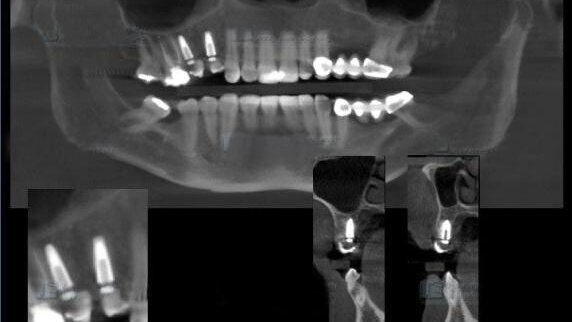

4. Fase Radiológica CBCT Una vez tomados los registros al paciente, éste fue enviado a la sala de radiología para tomarle un CBCT "Disparo Cónico en 3D" del sector donde tenía situado los implantes, concretamente con un FOV de 4x4. La toma se realizó con la inmovilización total de la cabeza del paciente del CBCT y se obtuvo un fichero DICOM que fue enviado a ENGIMAGE vía internet para su posterior procesado y alineación con los ficheros STL resultantes de las impresiones.

5. Procesado y tratamiento de datos en ENGimage Una vez el protésico hubo escaneado los registros anteriores y estos fueron transformados en un archivo STL, éste es enviado a los centros de ENGIMAGE para que junto el archivo DICOM resultante del CBCT fueran alineados por nuestros técnicos, obteniendo la siguiente información protésica: situación y orientación de los implantes, fotografía basal de la encía, dientes antagonistas, línea media, dimensión vertical y oclusión. Esta información será inmediatamente reenviada al laboratorio para el posterior diseño de la prótesis mediante software específico.